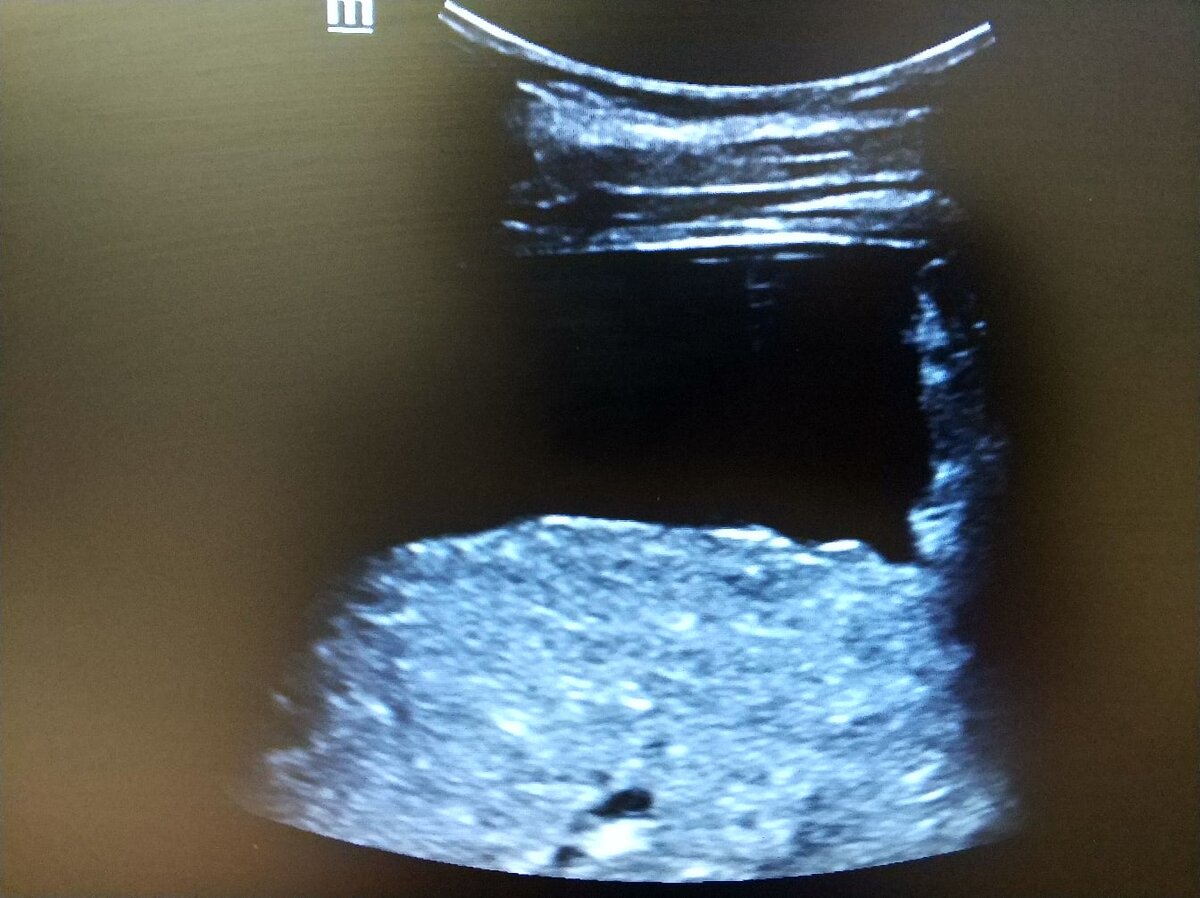

❓Видно ли цирроз на УЗИ❓

Именно так, видно.

🖼️Типичные проявления: симптом пунктира, выпот, высокий цирротический индекс.

🖼️Typical manifestations: dotted symptom, effusion, high cirrhotic index.